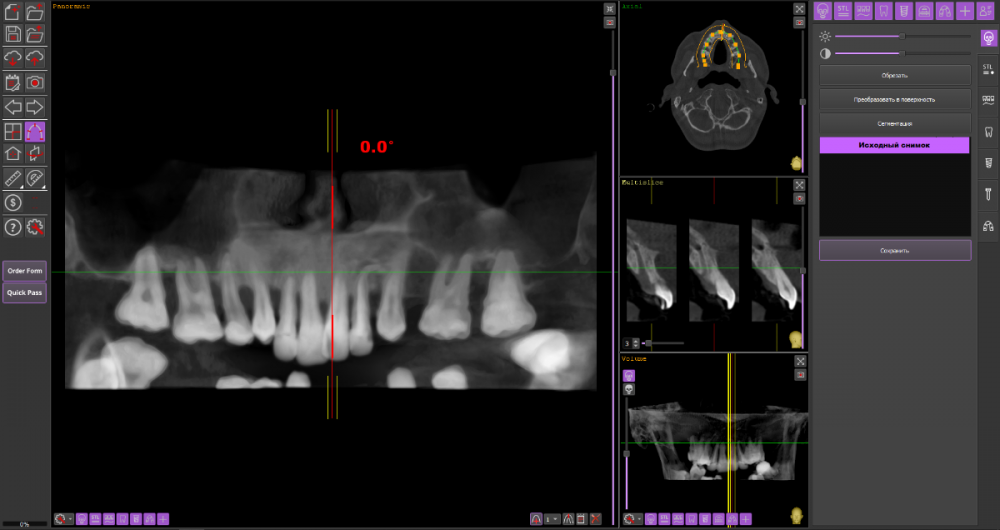

Сергей34 Опубликовано 13 октября, 2022 Автор Поделиться Опубликовано 13 октября, 2022 1 час назад, It'sGeorgy сказал: Вы правы. Перед установкой имплантатов снизу, зубы на верхней челюсти необходимо, как минимум, санировать и стабилизировать пародонтит. Само собой, необходимо учитывать состояние верхних зубов. Возможно, там уже санировать нечего и тогда крайне желательно делать обе челюсти вместе. Точнее без снимков сказать что-то невозможно. Вот верхняя челюсть. Кости как мне сказали тут почти нет и тут светит только протез обычный. https://we.tl/t-vedmhk4V7V Вот нижняя челюсть. https://we.tl/t-lwXRKsvL60 Тут как сказали можно всё на 4. Ссылка на комментарий

wladdX Опубликовано 14 октября, 2022 Поделиться Опубликовано 14 октября, 2022 верхняя челюсть нижняя челюсть 1 Ссылка на комментарий